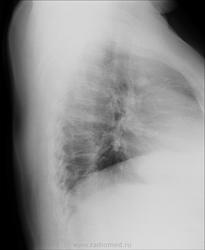

Женщина, 64года, пришла на прием с жалобами на длительный кашель. Снимки не очень качественные и без описания. Помогите разобраться. Признаки застоя? Интенсивная очаговая тень слева это что?

имхо: слева параортально петрификт.Признаков застойных изменений не вижу.

См. рис. Обызвествленный ЛУ. Поддерживаю коллег.

ИМХО. Петрификат - обызвествленный лимфатический узел, а очаг Гона - обызвествленный   участок первичного поражения легочной ткани.

Участок дистрофии или некроза ткани, инкрустированный солями кальция можно называть петрификатом(petrificatum; греч. petros камень + лат. facio делать) , кальцинатом, обызвествленным очагом (фокусом). Очаг Гона - обызвествленный, петрифицированный, кальцинированный первичный аффект в лёгком.